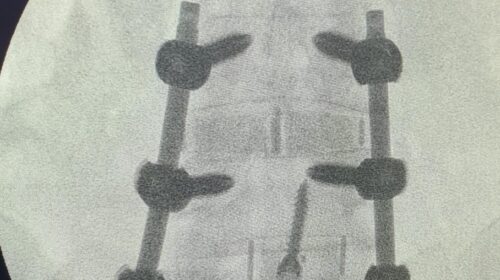

“Fueron tres tipos de exposiciones. Una de ellas es la cirugía en vivo, donde realizamos dos procedimientos en pabellón, acompañados por destacados especialistas, el Dr. Carlos Zanardi, presidente de la Sociedad de Neurocirugía de Buenos Aires, Argentina y el Dr. Cristiano Meneses, director del Instituto de Columna de Brasil”, precisó el Dr. Muñoz.

A continuación, compartimos las fotografías enviadas por el Dr. Avaria a la Sociedad de Neurocirugía de Chile: